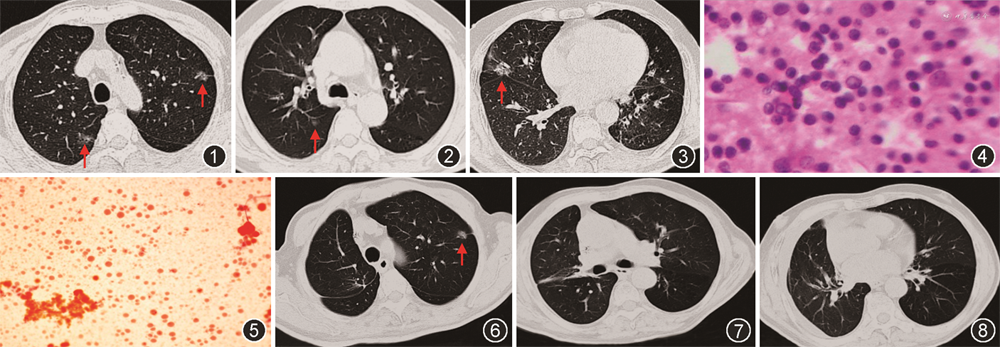

患者男,66岁,因“右肺癌术后5个月,胸闷气促4个月”于2019年11月15日入院。患者2019年5月6日肺部CT检查示右肺中叶结节,大小为1.7 cm×1.6 cm,呈混杂磨玻璃密度,其内可见血管穿行及支气管充气征,双肺多发磨玻璃结节(图1~3)。2019年6月8日行胸腔镜下“右肺上叶后段切除+右肺中叶切除+淋巴结清扫术”。术后病理示:右肺上叶后段和中叶共3处浸润性腺癌(腺泡型和贴壁型);右肺上叶后段1处原位腺癌,肿瘤均未浸润脏层胸膜,未见脉管内癌栓,支气管切缘及清扫淋巴结未查见癌。行EGFR检测21位点L858R突变。术后4 d拔除引流管出院。术后1个月患者逐渐出现胸闷气促,7月24日肺部CT示右侧大量胸腔积液,给与穿刺引流淡黄色澄清胸水后症状改善。9月14日再次出现大量胸腔积液,给予胸腔穿刺置管引流淡黄色清亮积液,先后3次胸腔积液病理未查到癌细胞,胸腔积液持续生成,10月1日给予培美曲塞1.0 g化疗1次,先后4次右侧胸腔注入顺铂(60 mg/次)治疗,口服吉非替尼250 mg,1次/d,经过上述治疗胸腔积液仍未控制,持续引流淡黄色胸腔积液。11月5日行正电子发射体层成像(PET-CT)检查,未见肿瘤转移征象,左肺上叶尖后段磨玻璃密度结节较前无变化。既往于2019年4月16日行胃间质瘤手术,病理示胃肠道间质瘤(GIST,梭形细胞型),肿瘤单发,术后口服伊马替尼400 mg,1次/d。

停用伊马替尼2周,限制食盐摄入并给予利尿剂治疗,患者胸腔积液生成仍未减少。胸腔积液甘油三酯0.34 mmol/L,反复3次胸腔积液乳糜试验均阳性(苏丹Ⅲ染色阳性,图5),考虑诊断肺癌术后迟发性乳糜胸。给予低脂饮食,脂肪乳支持治疗,同时给予奥曲肽治疗(100 μg,皮下注射,8 h/次,持续14 d),反复胸腔内50%葡萄糖注射(每次100 ml),经过治疗胸腔积液生成减少,拔除胸腔引流管。2020年3月25日超声检查探及右侧胸腔最大深度75 mm的游离无回声区,内透声差,见条索状强回声分隔,胸腔穿刺抽液为淡血性积液,离心沉渣蜡块病理未查见肿瘤细胞。于3月28日行胸腹部强化CT:肺部无新发结节及转移性病变(图6~8),左肺上叶结节病变无变化,仍无恶性胸腔积液依据。最终考虑为肺癌术后迟发性乳糜胸。